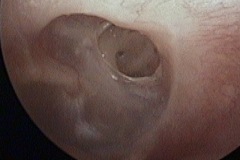

Perforation